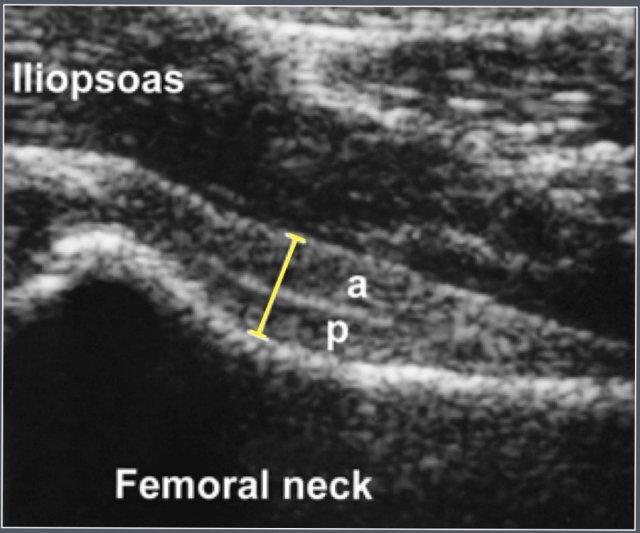

Bao khớp phía trước được đo bao gồm cả lớp trước và lớp sau. Đường viền phía trước của bao khớp cũng được đánh giá.

Đo bao khớp phía trước bằng siêu âm.

Cả lớp trước (a) và lớp sau (p) đều có thể được xác định.